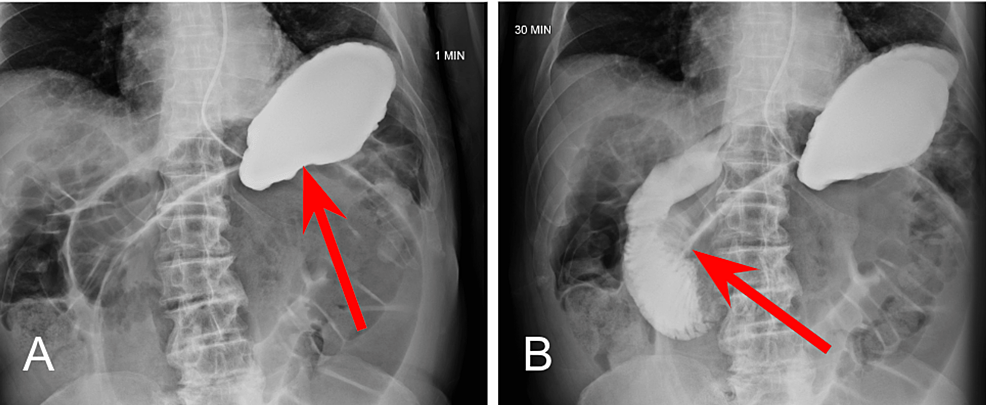

At the four-hour mark, enteric contrast is noted within the mid to distal small bowel (Figure 3A), with dilated loops of large bowel without contrast distally (Figure 3B). Without passage of oral contrast at the four hour mark, our suspicion for SBO located at the distal jejunum and proximal ileum was confirmed.